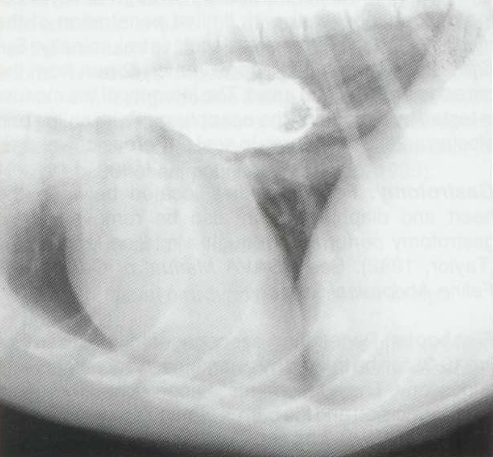

바륨 조영으로 lucent하게 나타난 이물 : filling defect의 형태